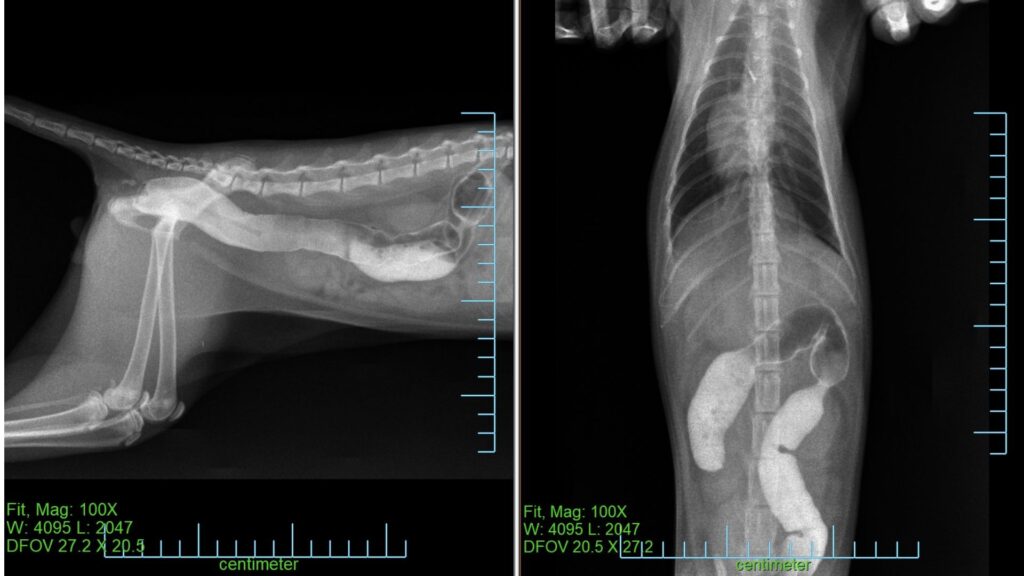

レントゲン検査

→明らかな異常は確認されませんでした

異物の通過状況を確認するため カストログラフィン(造影剤)を飲ませました。

この薬剤を使用することで、レントゲン検査で消化管の流れを確認することができます。

翌日以降に再度レントゲン検査を行い、腸内の通過状況を確認することとしました。

レントゲンでは造影剤が大腸まで到達していることが確認されました。